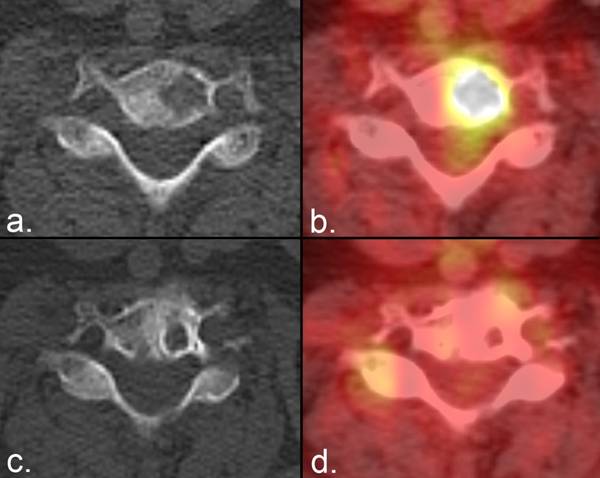

Figure 5

Partial response on radiographs according to the MDA criteria. (a) A lytic metastasis is seen in the C7 vertebral body on CT in a patient with breast cancer. (b) Fused PET/CT image from the same examination demonstrates FDG uptake representing active tumor. (c) Five weeks later, the lesion developed a sclerotic rim that resulted in a reduction in the size of the lytic area. (d) Fused PET/CT image from the same examination as (c) shows resolution of FDG activity, confirming the positive anatomic response.